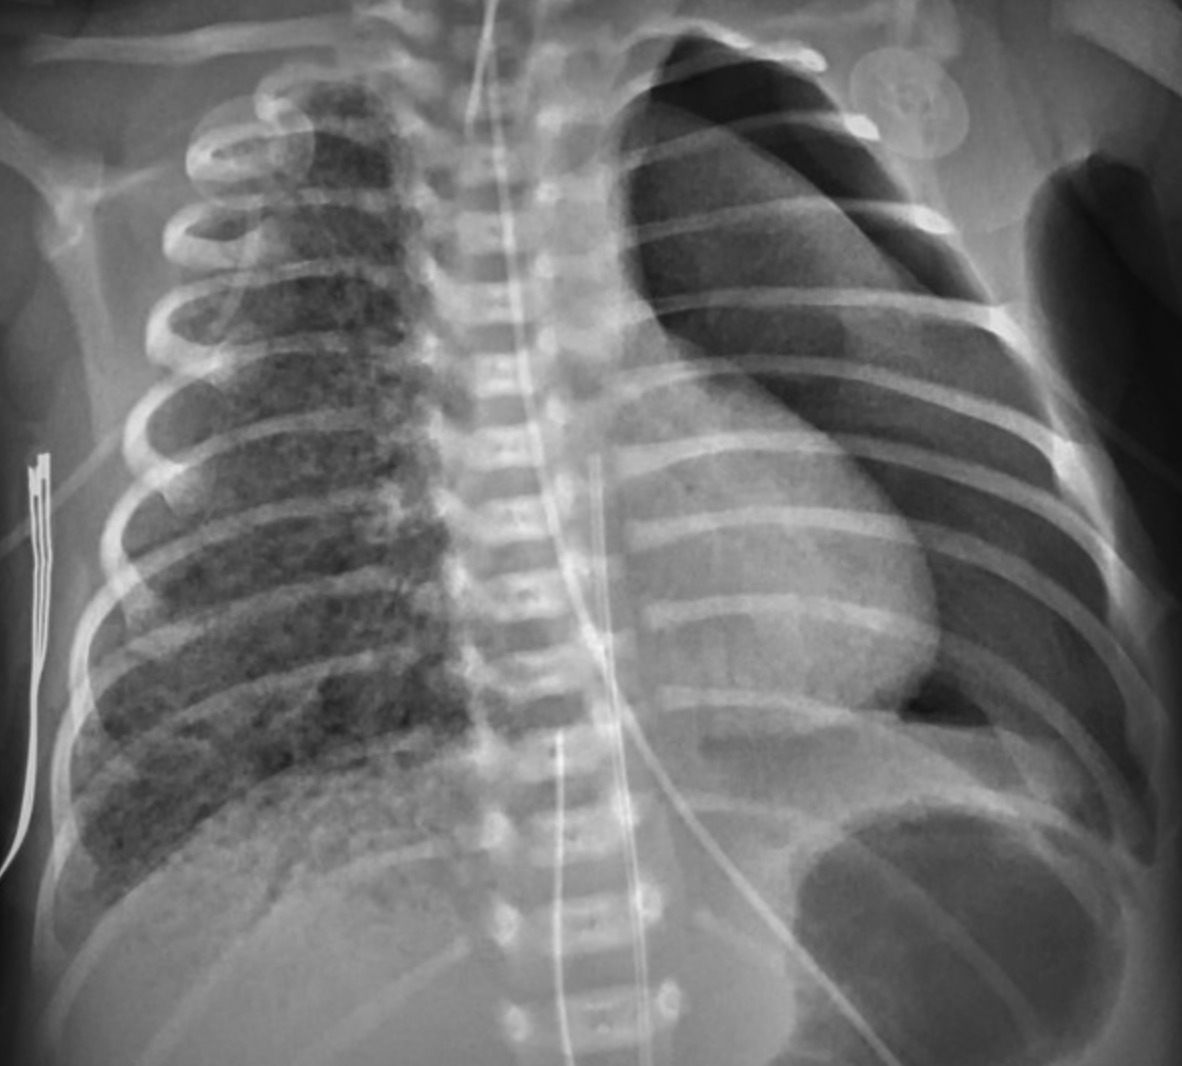

(X-Ray of neonate with PIE)

If PIE begins to develop also drop rate from 360 to 300 to 240.